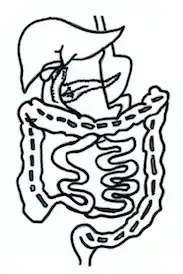

Biliopancreatic diversion

First appeared in 1980, biliopancreatic diversion involves two parts: gastrectomy and intestinal bypass. Firstly, gastrectomy removes a large portion of the stomach. Reduction in stomach capacity decreases the appetite of patients. Secondly, intestinal bypass anastomoses the proximal duodenum and the distal ileum. This intestinal bypass is different from the above three bypasses in the way that the blind loop carrying bile and digestive enzymes will drain into the distal portion of the small intestine. With this technique, the absorption of nutrients, in particular, fat, can be reduced tremendously.[6]